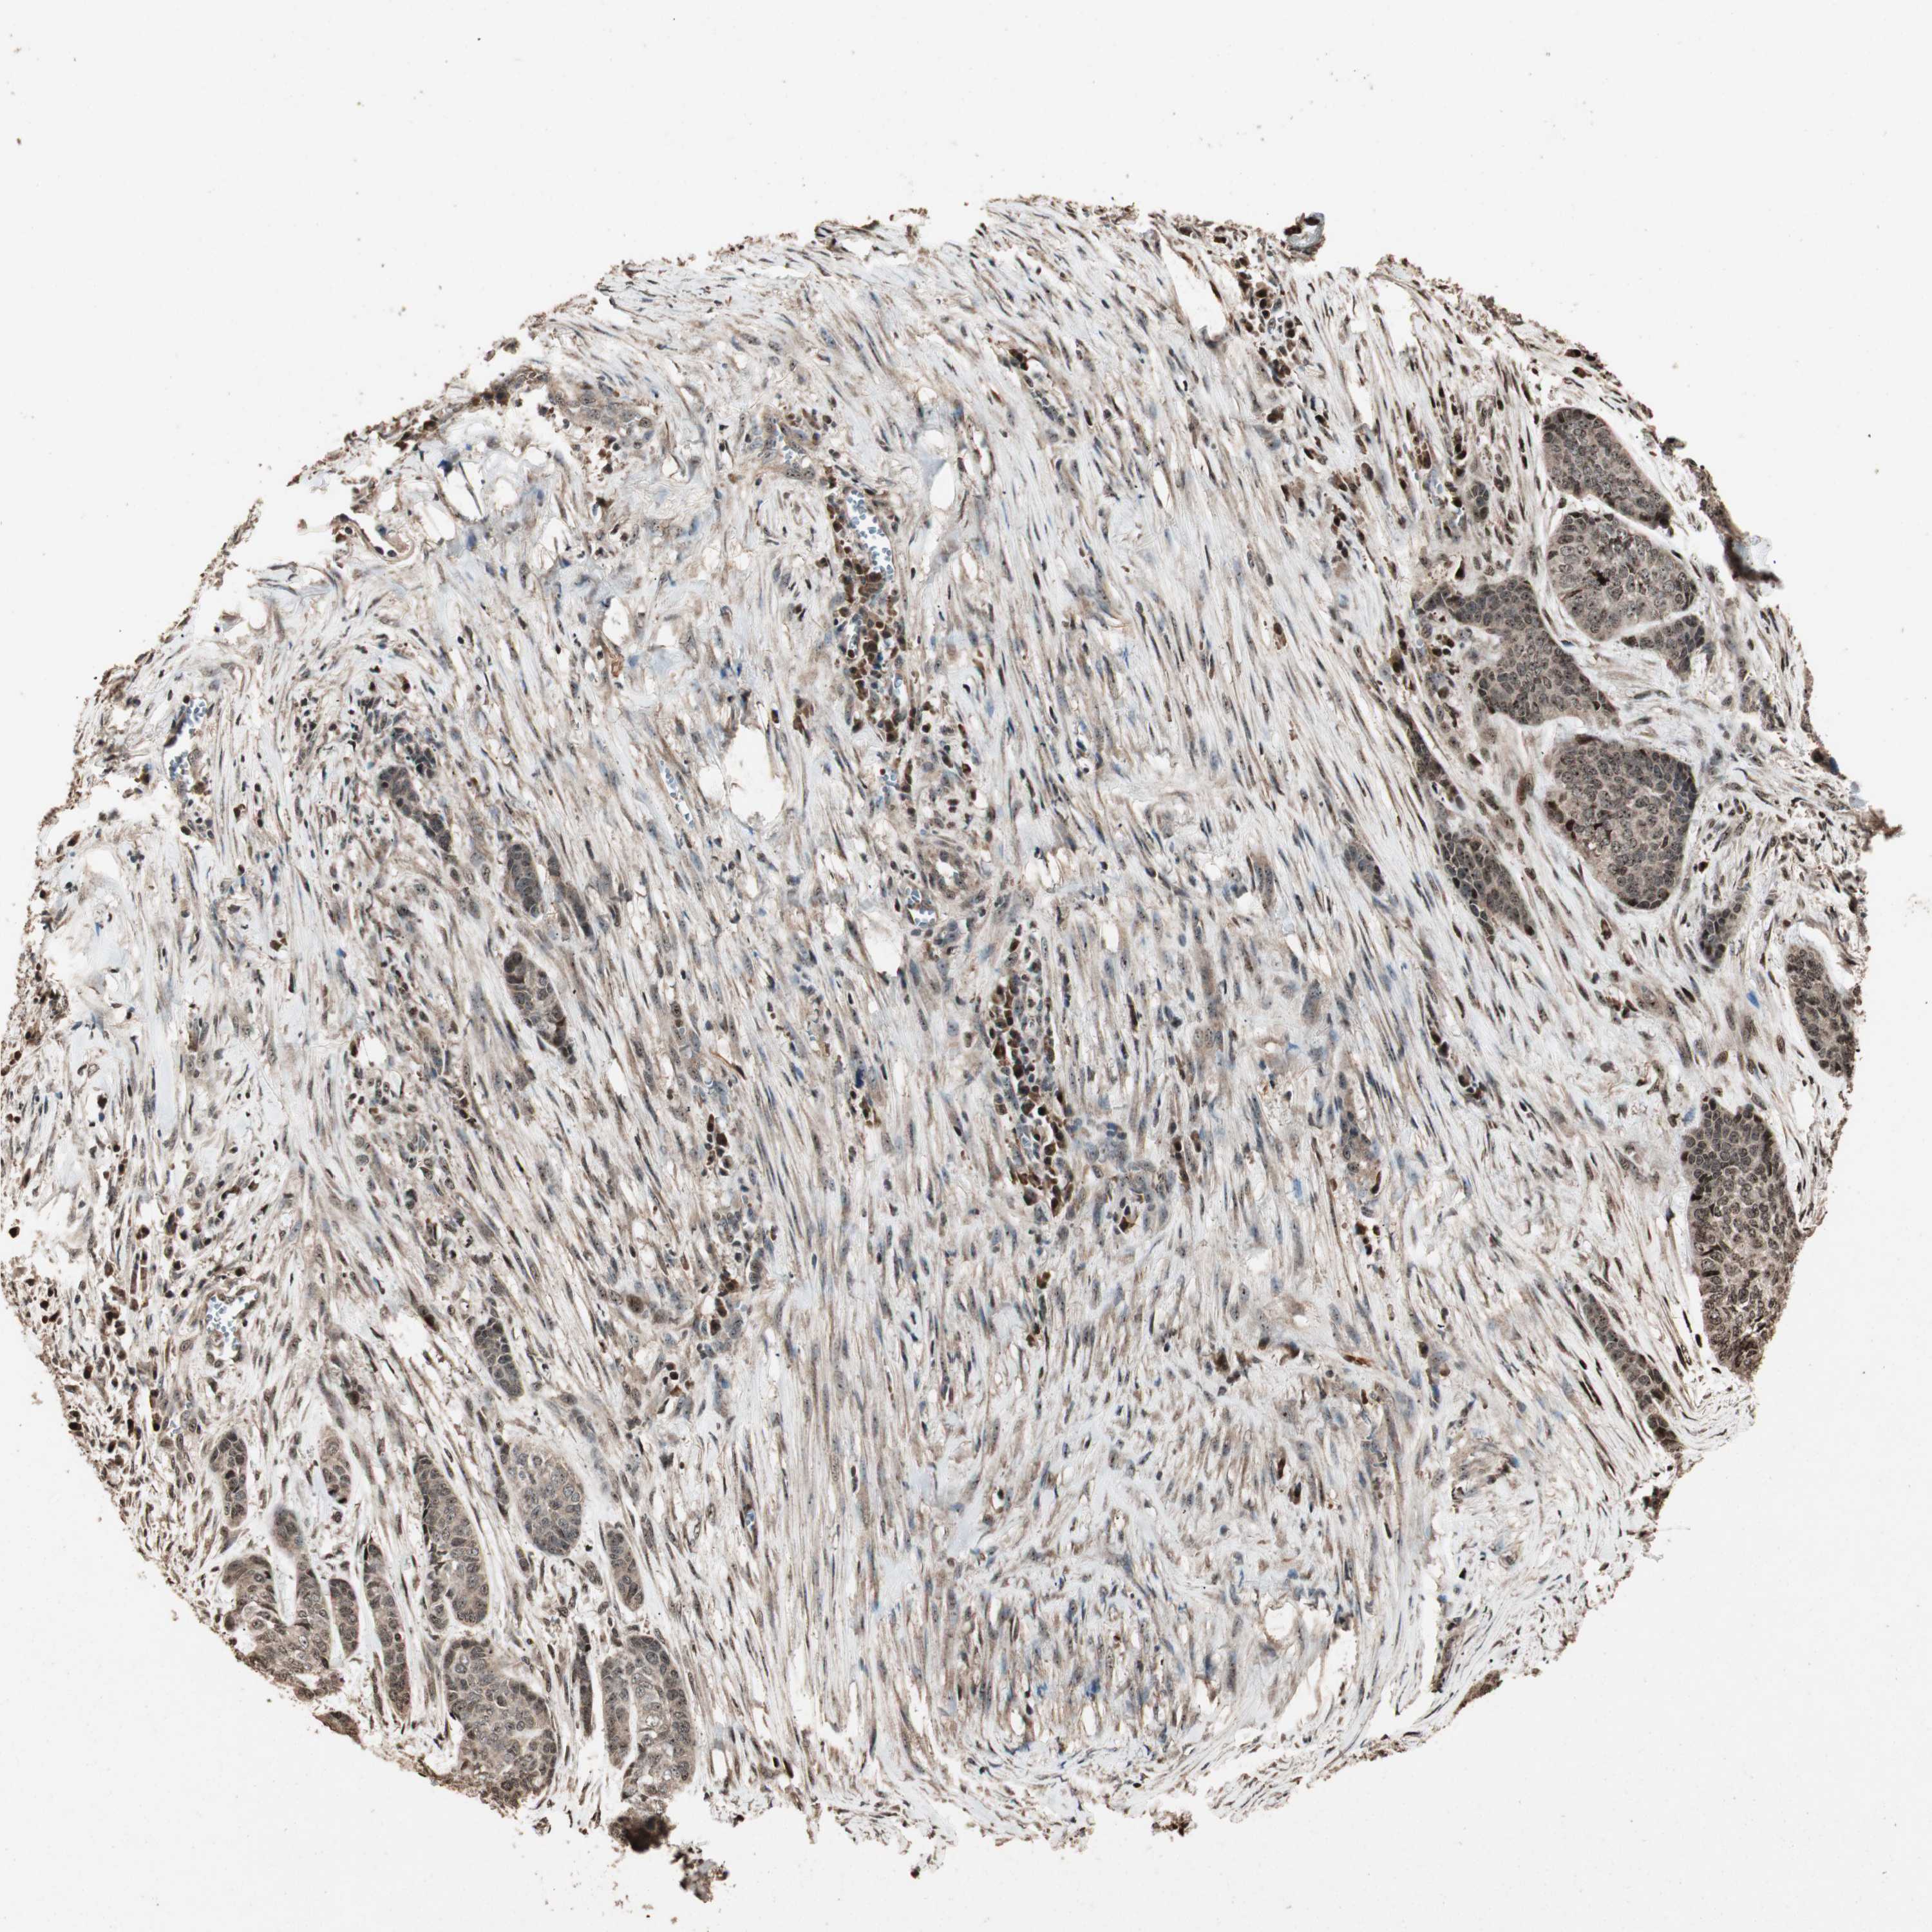

SKIN CANCER - Protein expressioni

A mouse-over function shows sample information and annotation data. Click on an image to view it in a full screen mode. Samples can be filtered based on level of antibody staining by selecting one or several of the following categories: high, medium, low and not detected. The assay and annotation is described here.

Each image is clickable and will lead to virtual microscopy that enables deeper exploration of all samples and also displays staining intensity scores, fraction scores and subcellular localization as well as patient and tissue information for each sample.

Antibody HPA006287

Staining

Medium

Intensity

Moderate

Quantity

75%-25%

Location

Cytoplasmic/membranous

Squamous cell carcinoma, NOS